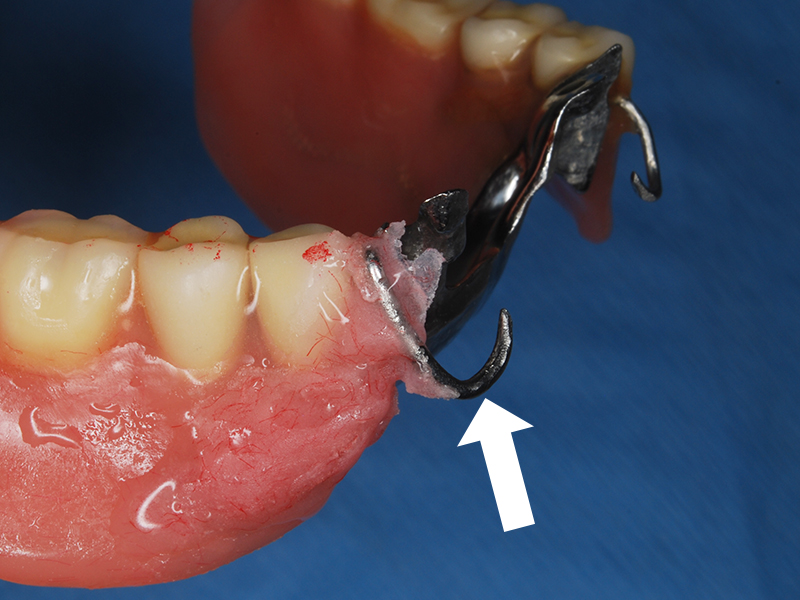

義歯修理の例

義歯維持装置(クラスプ)の欠けた部分

修理部分に凹みをつけ装着して型を取る

模型上で凹み部分にクラスプ新製

凹みの仮封鎖を取りクラスプ適合確認

義歯に組み込みレジンで固める

クラスプ修理の出来た義歯

修繕義歯の装着

通常の義歯修理は上の例のようにプラスチック部分に補強線や義歯の維持装置を組み込むことが殆どですが、金属の精密な義歯をお使いの場合は、現状を変えることなくレーザー溶接や高周波スポット溶接等も利用することがあります。